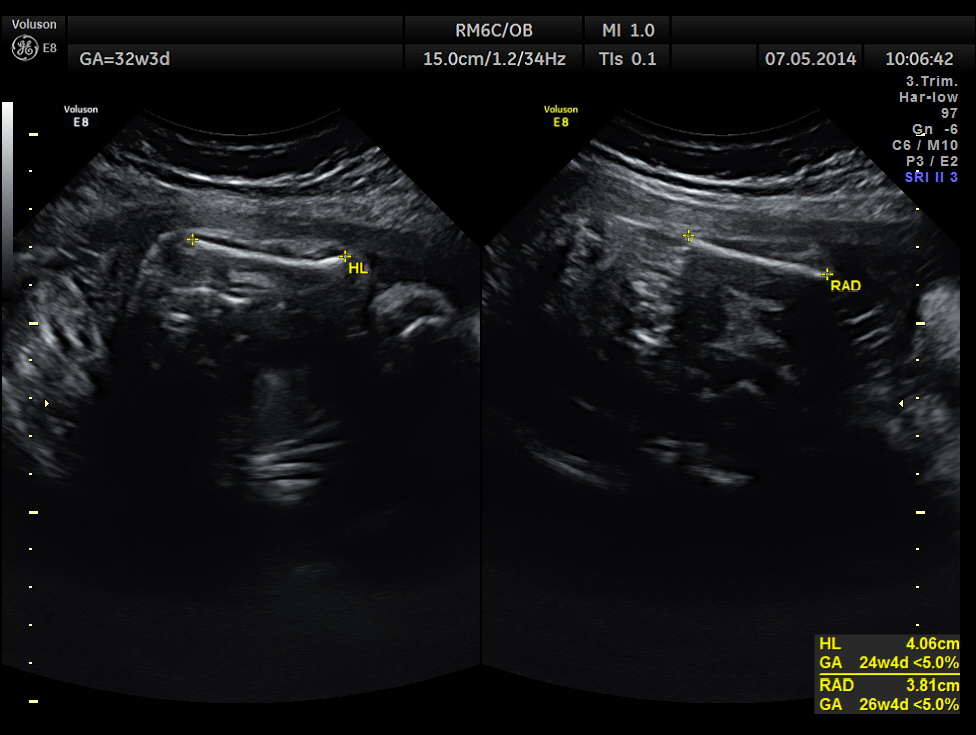

This was a 37 year old lady , a primi gravida referred for evaluation of intra uterine growth restriction. As per LMP the GA was 32 w 3 Days, but as per AUA the GA was 26 weeks . All the long bones were < 5.0 % tile. But cerebellum was 42.7 % tile. There was severe symmetrical growth restriction .

The echo pictures are given below.